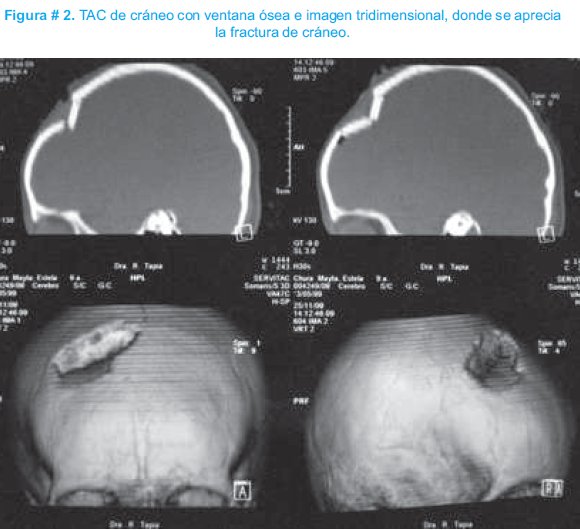

Paciente femenino de 9 años de edad quien consultó en el Hospital del Niño "Dr. Ovidio Aliaga Uría" en noviembre del 2008, por un cuadro clínico de 18 horas de evolución, caracterizado por presentar una lesión la región frontoparietal derecha secundaria a un traumatismo con una piedra, herida con solución de continuidad, vómitos en varias oportunidades y pérdida de conocimiento por aproximadamente 15 minutos. Al examen físico se encontraba irritable, consciente y orientada, sin datos de focalización, Glasgow de 15 y la presencia de una herida en la región antes mencionada de 5 cm de longitud, que compromete piel, tejido celular subcutáneo y músculo y sensación de hundimiento craneal a la palpación. Se realizó una tomografía axial computarizada (TAC) simple de cráneo donde se apreció una fractura con hundimiento de cráneo, fragmentos óseos en cerebro y edema cerebral difusor; como se observan en las figuras # 1 y 2. Ingresó con los diagnósticos de fractura frontoparietal derecha expuesta con hundimiento de cráneo y traumatismo craneano severo. En cirugía se realizó: sutura de un desgarro de la duramadre, retiro de fragmentos óseos incrustados en cerebro, levantamiento del hundimiento craneal con fijación de los segmentos óseos y cierre por planos de los tejidos blandos. Fue tratado con cloxacilina y manitol y la evolución fue favorable.